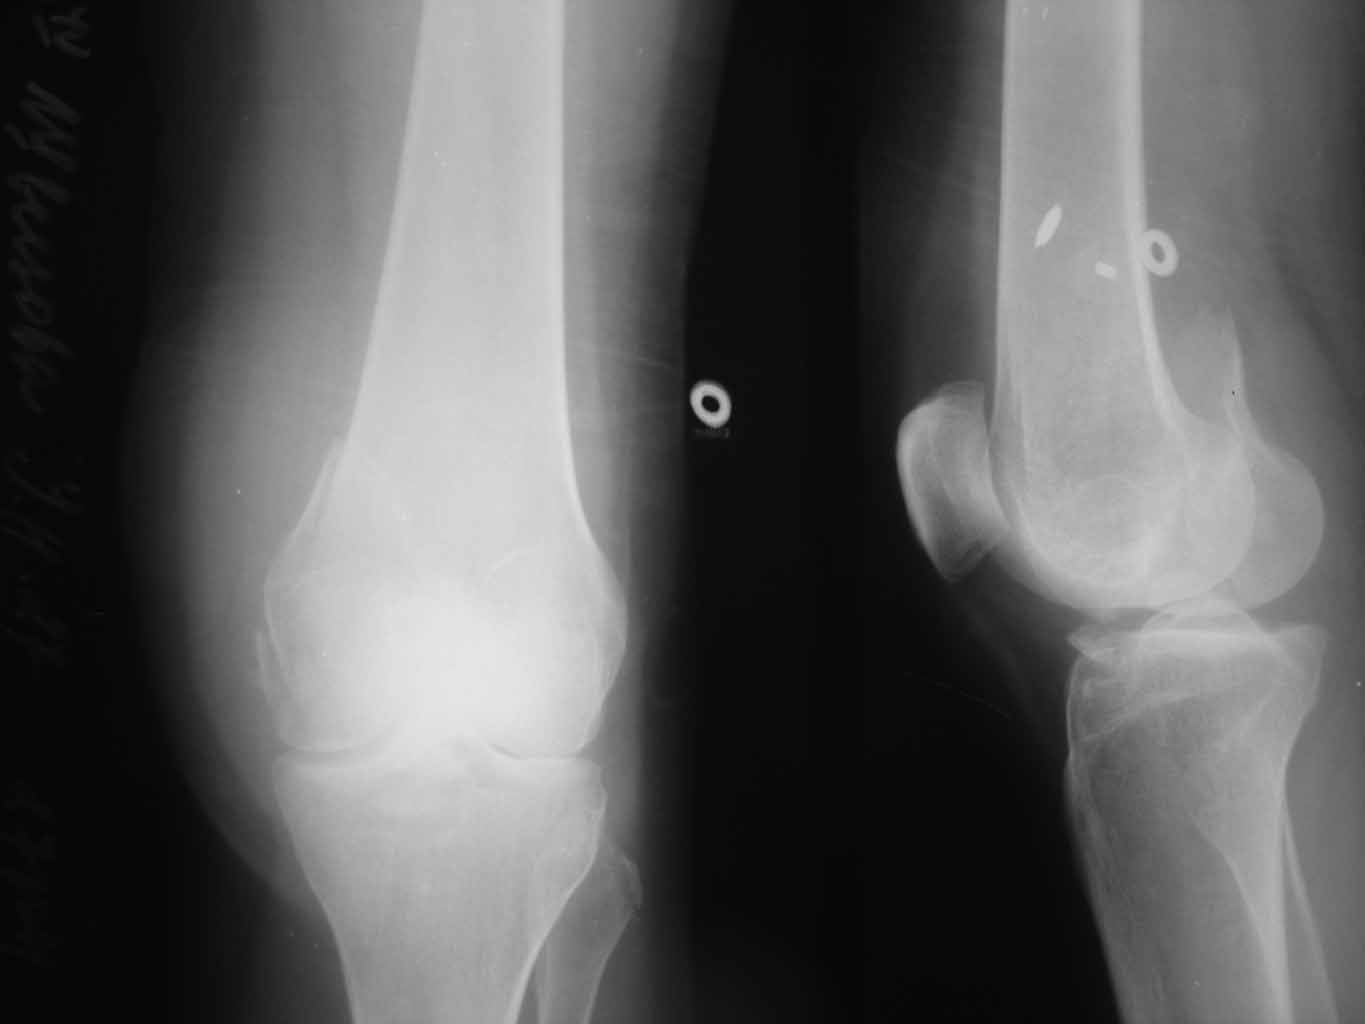

Уважаемые коллеги!!!!Хотелось бы услышать мнения...Закрытый перелом медиального мыщелка бедра от 28.10.11. Здравствуйте, уважаемые коллеги! Просим помочь!!! В отделение поступила пациентка 27 лет с переломом медиального мыщелка бедренной кости, была сбита автомобилем. Планируем оперативное лечение. Подскажите пожалуйста, какой фиксатор предпочтительнее выбрать при данной локализации перелома, каким доступом выполнить репозицию отломка, возможна ли фиксация отломка дистальной бедренной пластиной, есть ли фиксаторы именно для медиального мыщелка бедра? ЭОП есть, финансовые возможности у пациентки есть. Если у вас найдутся рентгенограммы похожих случаев, пожалуйста, скиньте в обсуждение, будем очень признательны. Спасибо! Ждем ваших комментариев!

Обратите также внимание на перелом головки малоберцовой кости и фрагмент передней части межмыщелкового возвышения - это может быть повреждение связок: ПКС и наружной боковой.